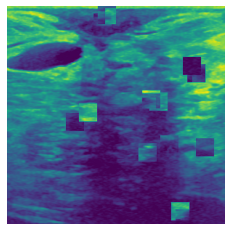

In figure 3, we present qualitative examples of different masking strategies. It is observed that, unlike context prediction and restoration, our method tends to propose targeted masks like the tumor regions or regions with abnormalities and avoids masking less helpful regions. However, it should be noted that Intelligent-Masking does not necessarily mask the tumor regions but considers all areas of interest that results in better feature learning. Examples of other masking samples are provided in supplementary materials. Furthermore, in medical images, unlike natural scenes, the structures are very local with imbalanced information throughout an image. Therefore, random masking strategies as shown in Fig 3 operate ineffectively by masking non-informative regions.

Figure 2: Qualitative examples of compared method’s strategies for masking

Figure 3: More qualitative examples of different distorting strategies including our method. We show the different self-supervised mechanisms on both datasets of MR (rows: 1-3) and ultrasound (rows: 4-6) images for lower-grade glioma and breast cancer diagnosis respectively. We include both images of normal (rows: 1,4) and cancer (rows: 2,3,5,6) conditions for each dataset. We also observe that our method treats each image based on its context information with no predetermined strategy.